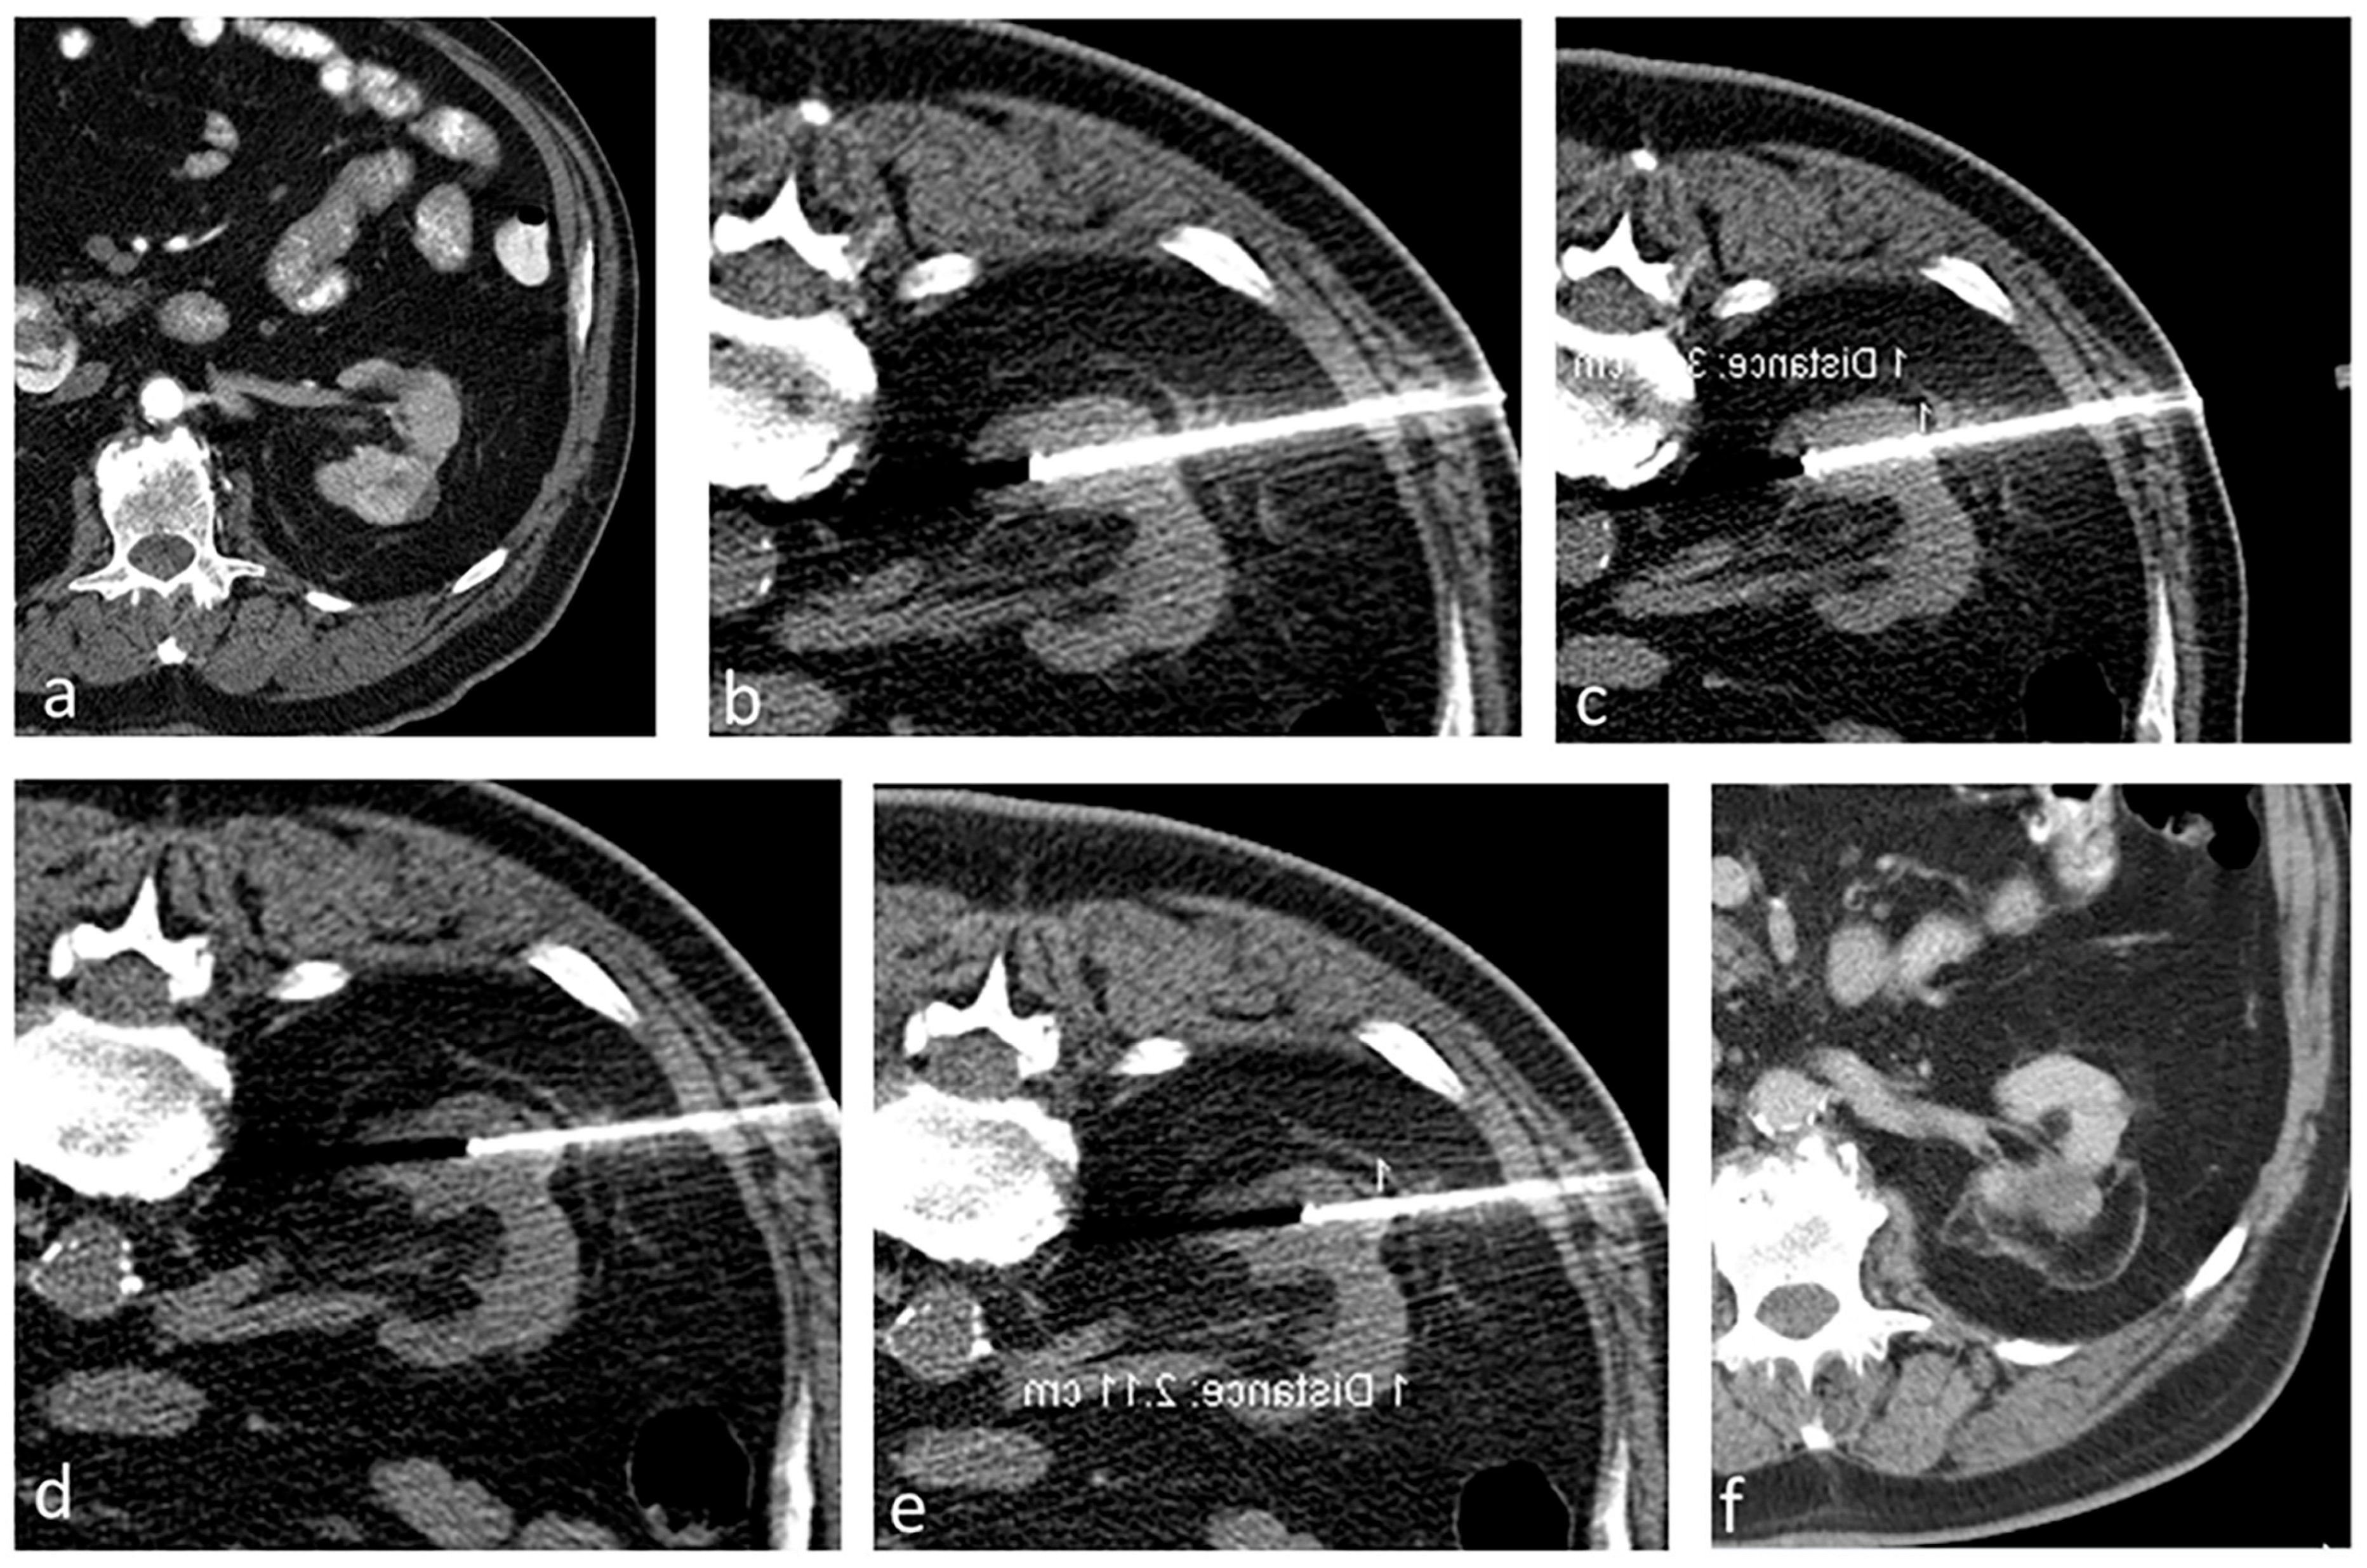

Immediately after the ablation, we carry out a multi-phase contrast-enhanced CT to evaluate the ablation area and detect any immediate complications. Thereafter, we schedule follow-up imaging at regular intervals for a period of 2 years, followed by annual checks. Figure 2 shows a case in the study that has a transverse diameter of 3.9 cm treated by the aforementioned technique.

Figure 2.

A patient with a 3.9 cm biopsy-proven RCC treated using RFA. (a) Contrast-enhanced CT showing a renal mass (3.9 cm in transverse diameter) in the left kidney. (b–e) Ablation procedure. (b,c) Non-contrast axial CT showing the probes positioned to treat the deeper portion of the tumor, and subsequently the probes were retracted to treat the superficial portion of the tumor (d,e). (f) Contrast-enhanced CT after 5 years showing no evidence of residual or recurrent tumor in the left kidney.